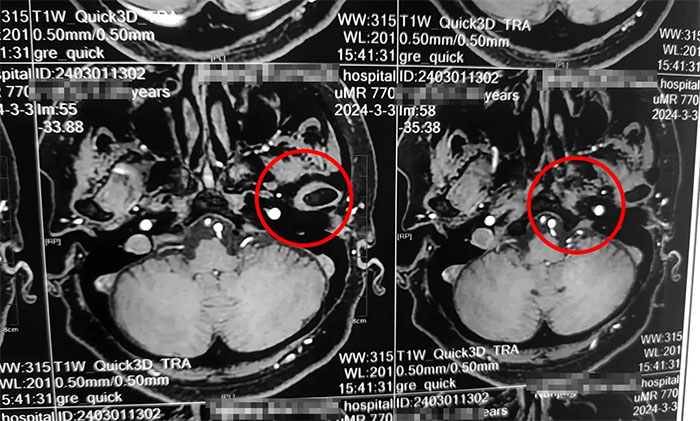

杨忠旭教授详细了解了刘阿姨的症状、病史资料、影像资料等。杨忠旭教授分析指出,传统的三叉神经痛大多发生于面部,而刘阿姨疼痛的部位为舌头,和最普遍的三叉神经痛位置大相径庭,但其实支配舌前2/3的感觉的舌神经,也是自三叉神经发出,所以此处的疼痛完全符合三叉神经痛的表现。结合影像资料,杨忠旭教授指出患者左侧三叉神经根部与临近小血管关系密切,手术指征明显,未见明显手术禁忌症。

▲ 左侧三叉神经与临近小血管关系密切